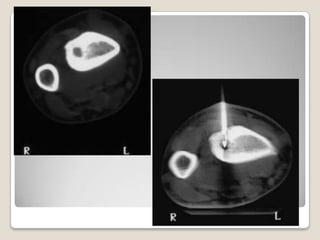

TAC

TAC contrastada para

Nidos < 2 - 3mm en

columna y cadera se

detectan mejor con TAC

TAC   TAC contrastada para diferenciarlesión de un proceso infeccioso Nidos < 2 - 3mm en columna y cadera se detectan mejor con TAC